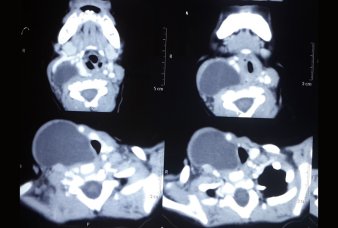

Large Branchial Cyst

CT Scan showing the large Branchial Cyst